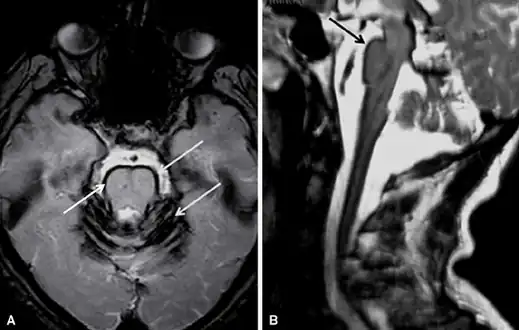

Early detection of superficial siderosis is usually via MRI. The iron deposition that is characteristic of superficial siderosis shows up as a hypointense band in affected tissues, with a characteristic rim of intensity appearing on the cerebellum; a hyperintense rim is rarely seen.[8] Taking samples of cerebrospinal fluid may also reveal siderosis through xanthochromia, elevated presence of red blood cells, high iron and ferritin concentrations, and elevated levels of the proteins Tau, amyloid beta (Aβ42), neurofilament light chain (NFL), and glial fibrillary acidic protein (GFAP), but the CSF is sometimes normal.[10] Detection is complicated by the fact that superficial siderosis is a rare disease and is not well described in neurological texts, so it may go unnoticed until noticeable symptoms appear.[11]

Brain MRI of a individual with superficial siderosis -